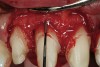

Figure 15  After removal of the defective restoration, it can be seen clinically that the margin of the preparation on the distal of tooth No. 21 was extremely subgingival. The surrounding periodontium was inflamed and hemorrhagic. The laser was used to perform apical repositioning of the bony crest using a closed-flap technique.

Figure 15

Figure 16  After initial positioning of the bone, keeping the tip of the laser in intimate contact with the root surface, a slight troughing of the bone was seen on radiographic examination.

Figure 16

Figure 17  The tip of the laser was angled slightly to the distal and moved away from the root surface to smooth and blend the adjacent bony surfaces.

Figure 17